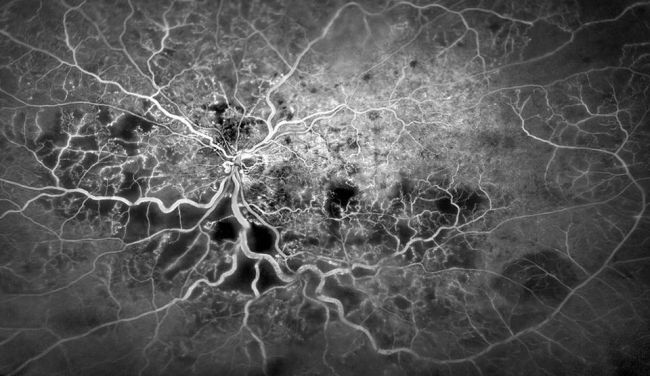

Interiorul vaselor de sânge ale globului ocular uman

„Aici este reprezentat interiorul unui vas de sânge situat în zona inferioară a ochiului uman. În mod normal, nu putem să observăm sângele, deoarece acesta circulă cu o viteză mult prea mare pentru a fi imortalizat. În timp ce se deplasează, el modelează structura interioară a vasului de sânge, dându-i o formă aparte”, a punctat Robin Lovell-Bridge.

Foto: bbc.com/Peter Maloca/University of Basel